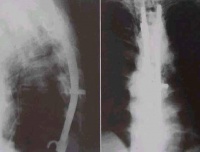

(二)骨形改变。管状长骨的破坏可表现为不同程度的膨胀变形,脊椎的椎体结核、椎体坍塌可呈楔状变形,椎体上下之间相互嵌入出现驼背或龟背畸形等。

(三)关节改变。关节软骨被破坏可使关节间隙狭窄,软骨破坏后不会再生,狭窄发生后会长期存在。脊椎椎间盘破坏不能再生,如破坏明显,椎间隙永久性消失

脊柱是骨结核最常见的发病部位,尤其是在老年人群;但是在发展中国家,儿童和青少年发病的也很常见。有些病人能发现肺或泌尿系有原发结核病灶,也有些病人找不到原发灶。淋巴和血行播散的结核一般发生在胸腰段,很少播散到颈椎和骶骨。脊柱结核的活动性病变破坏特定的椎体节段:通常是相临的两个椎体和椎体之间的间盘。一些研究者推测,病变破坏的这种特点的原因是:该部位动静脉血供丰富,而结核杆菌需要高的氧分压。

约80%的病人为间盘周围病变,侵及椎体前部,最后经韧带下间隙(前纵韧带)发展到相临的椎体。少数病人病变发生在椎体中央,这种病变可类似肿瘤或者引起明显的脊柱畸形,有时很难诊断。病人可能会有髓内肉芽肿、蛛网膜炎、椎体节段性塌陷形成的前方楔形变、驼背(Pott病)等。单纯的脊柱后部结构结核很少见。有时会形成椎旁脓肿并形成皮肤窦道,侵及同一平面的腹腔脏器。椎旁脓肿最远可到达腘窝。病人会有疼痛、无力,到晚期会出现截瘫。